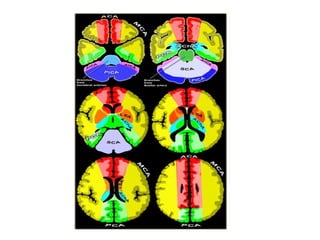

b) Cerebral Arterial Territory :

1-Posterior Inferior Cerebellar Artery

2-Superior Cerebellar Artery

3-Branches from vertebral and basilar artery

4-Anterior Choroidal artery

5-Lenticulostriate arteries

6-Anterior cerebral artery

7-Middle cerebral artery

8-Posterior cerebral artery

1-Posterior Inferior Cerebellar Artery (PICA in blue)

-The PICA territory is on the inferior occipital

surface of the cerebellum and is in equilibrium

with the territory of the AICA in purple which

is on the lateral side

-The larger the PICA territory , the smaller the

AICA and vice versa

2-Superior Cerebellar Artery (SCA in grey)

-The SCA territory is in the superior and tentorial

surface of the cerebellum

SCA , cerebellar infarction in the region of the superior cerebellar artery and

also in the brainstem in the territory of the PCA , notice the limitation to

the midline

-These branches supply the medulla oblongata

(in blue) and the pons (in green)